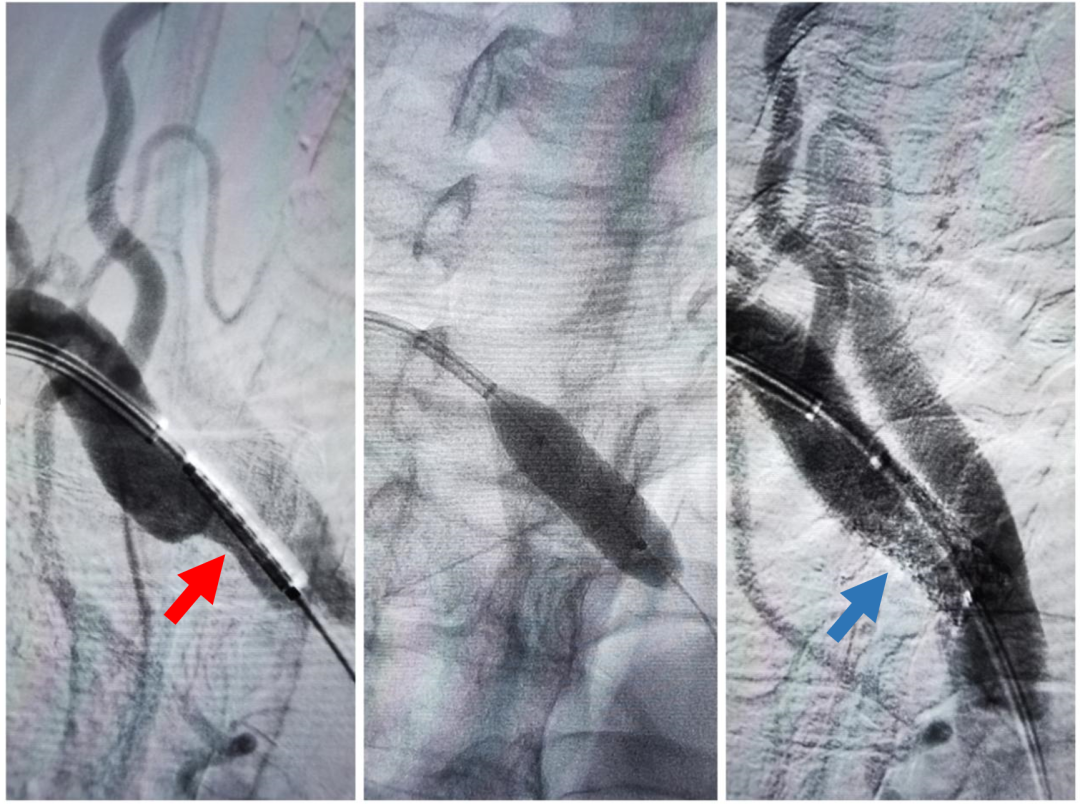

右侧锁骨下动脉起始段极重度狭窄、迂曲(红箭头)

球扩支架顺利置入,狭窄解除(蓝箭头)

张主任团队经充分的术前评估及术前讨论,手术经桡动脉入路进行。术中造影提示:右侧锁骨下动脉起始段重度狭窄(狭窄率约95%),狭窄部位血流呈线样通过;同期为患者行右侧锁骨下动脉支架置入术,手术过程顺利,无不良反应发生。